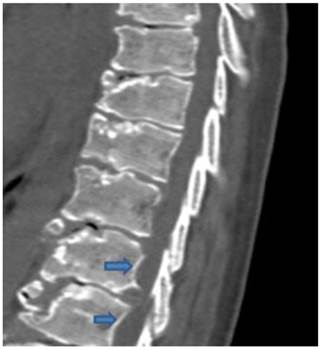

Sagittal reformatted spinal CT scan in a 9-year old boy showed, platyspondyly, extensive endplate sclerosis and anterior spurring and severe irregularities/fragmentations of the anterior and the posterior end-plates respectively associated with giant (bridging) osteophytes formation and Schmorl´s nodes overwhelmed by severe premature degeneration associated with narrowing of the intervertebral disc spaces. Note vertebral scalloping of the posterior vertebral wall along the lower lumbar vertebrae (arrows) (fig 2).

Fig 2

Sagittal reformatted spinal CT scan in a 9-year old boy showed, platyspondyly, extensive endplate sclerosis and anterior spurring associated with giant osteophytes formation, and Schmorl´s nodes associated with narrowing of the intervertebral disc spaces. Note the development of vertebral scalloping along the lower lumbar vertebrae (arrows).